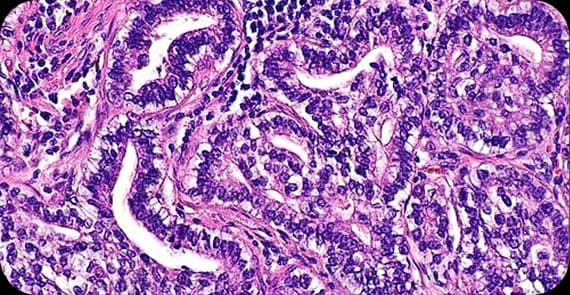

Cervical cancer is not a single disease. There are different types of cervical cancer based on the cells involved.

The most common type, arising from the thin, flat cells lining the outer cervix.

Develops from glandular cells that produce mucus in the cervical canal.

Contains features of both squamous and glandular cancers. Understanding the types of cervical cancer helps determine prognosis and appropriate treatment strategies.